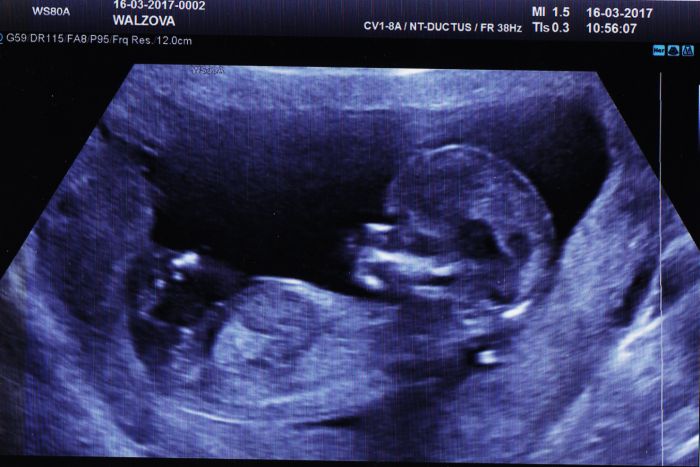

Tak dnes jsem byla na screeningu a vyšel NEGATIVNÍ!!!Hurráááá

Čekáme holčičku